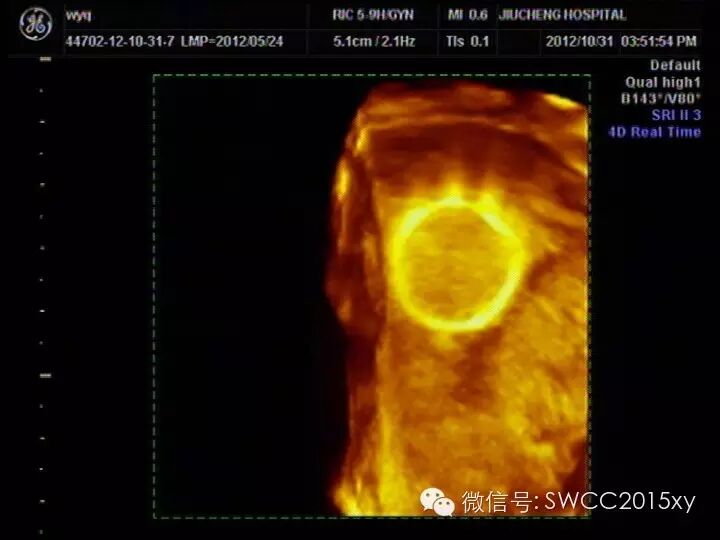

首先我们先了解一下环(节育器)是怎样避孕的(及环的功能作用):1:机械作用:作为一个异物,使子宫内膜发生一种轻度、慢性、非细菌性炎性反应,从而改变子宫内环境,阻止孕卵着床。 2:炎性细胞作用:炎性细胞的退变物质达到一定浓度后,毒害胚胎使之不能继续发育。 3:吞噬细胞作用:主要是巨噬细胞、中性白细胞发挥吞噬破坏精子的作用。 4:活性物质作用:宫内节育器可由金属铜制成,它可以通过宫腔内膜、宫腔液等内环境的局部变化,和对精子的毒性作用,来达到避孕目的。5:前列腺素作用:宫内节育器可刺激宫腔内膜产生前列腺素,前列腺素使子宫、输卵管收缩蠕动异常,同时增强雌激素作用,使宫腔内环境不利于着床。看看下图怀孕后宫内的节育器就像悬浮在空中的一个美丽的花环。